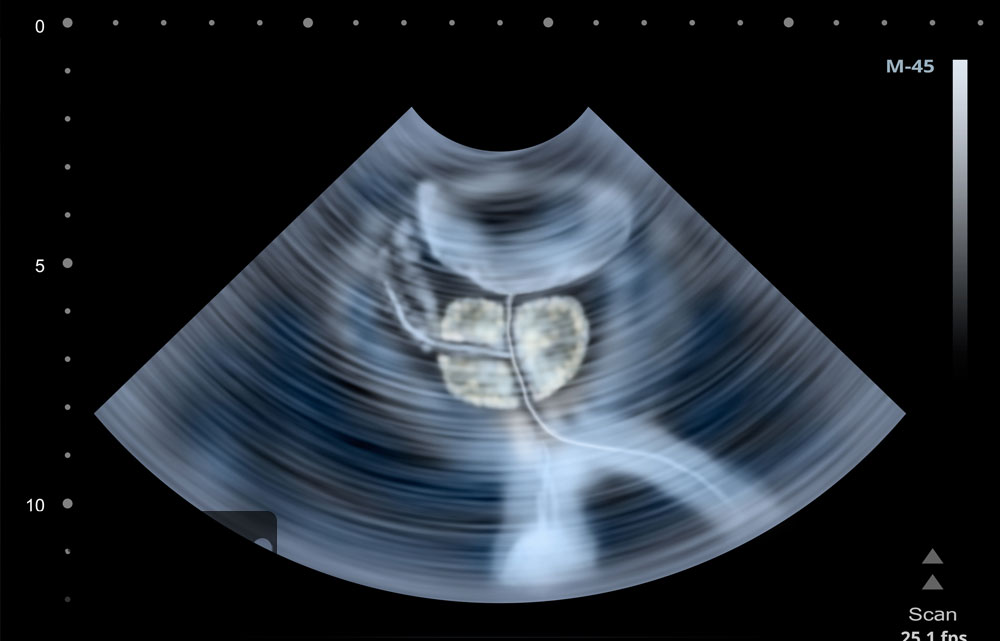

سونوگرافی پروستات یکی از روشهای پیشرفته در تصویربرداری پزشکی است که به بررسی دقیق بیماریهای پروستات کمک میکند. این روش با استفاده از امواج صوتی، تصاویری دقیق و واضح از دستگاه تناسلی مردانه و به طور خاص، پروستات ارائه میدهد. پزشکان از این تصاویر برای تشخیص پروستات و شناسایی مشکلات پروستات مانند هایپرپلازی خوشخیم پروستات (BPH)، التهاب پروستات یا حتی سرطان پروستات استفاده میکنند.

در این آزمایش پروستات، امواج صوتی بدون هیچگونه درد یا خطر، به بدن ارسال میشوند و بازتاب این امواج، اطلاعات دقیقی درباره اندازه، شکل و ساختار پروستات فراهم میکند. برای بررسیهای تخصصیتر، از روش ترانس رکتال یا همان سونوگرافی از طریق رکتوم استفاده میشود که به پزشک دید بهتری نسبت به تغییرات داخلی پروستات میدهد.

سونوگرافی پروستات به دو روش اصلی انجام میشود: سونوگرافی ترانس رکتال (TRUS) و سونوگرافی شکمی. هر یک از این روشها ویژگیها و کاربردهای خاص خود را دارند که در ادامه به آنها میپردازیم.

۱. سونوگرافی ترانس رکتال (TRUS)

در این روش، مبدل دستگاه سونوگرافی از طریق مقعد وارد میشود و تصاویر دقیقی از غده پروستات و بافتهای اطراف آن ارائه میدهد. این نوع سونو پروستات بیشتر برای تشخیص بیماریهای پروستات مانند سرطان پروستات، پروستات بزرگشده و حتی برای انجام بیوپسی پروستات استفاده میشود.